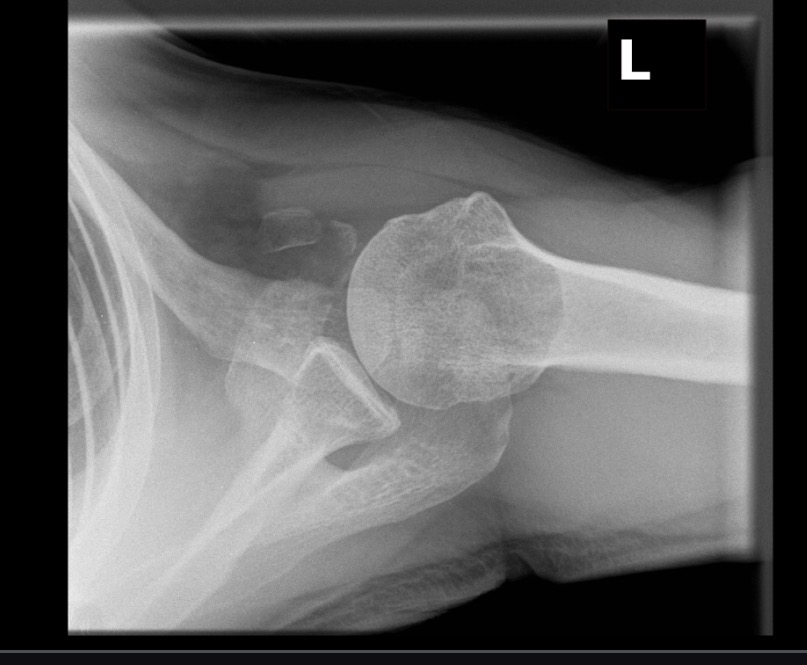

What projection position is this image?

Inferosuperior Axial of the Left Shoulder